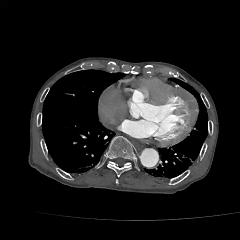

现病史:患者8小时前无明显诱因下出现头晕伴恶心呕吐,呕吐物为胃内容物,无视物旋转,无呕血黑便,无胸闷气促,无胸痛,遂至当地医院就诊查。CTA提示主动脉瘤,腹主动脉多发钙化,胸主动脉多发钙化斑块。

既往史:高血压数年,心脏病史